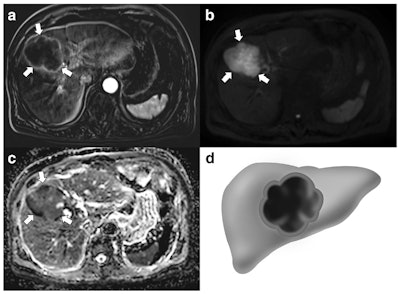

"Neuroendocrine tumors and their metastases to the liver and lymph nodes more frequently demonstrated a thick rim appearance on contrast-enhanced MRI and diffusion-weighted images," they reported. "The ratio of apparent diffusion coefficient values between the lesion and the spleen was significantly lower for the primary mass, liver metastases, and lymph node metastases of GB-NETs than for those of GB-ADCs. A large metastatic lymph node was the only poor prognostic factor for overall survival in patients with GB-NETs and GB-ADCs."

Of 63 patients, 21 had GB-NETs and 42 had GB-ADCs. Compared with GB-ADCs, GB-NETs more frequently demonstrated well-defined margins, intact overlying mucosa, and thick rim contrast enhancement and/or diffusion restriction on MRI scans. Liver metastases were more common and demonstrated thick rim contrast enhancement and diffusion restriction in GB-NETs, while lymph node metastasis showed thick rim diffusion restriction more often in GB-NETs than in GB-ADCs, the authors reported.

On quantitative analysis, the sizes of the gallbladder mass and metastatic lymph nodes in GB-NETs were larger than those in GB-ADCs (p = 0.002 and p = 0.010, respectively). The ratio of apparent diffusion coefficient values between the lesion and the spleen was lower in the gallbladder mass, liver metastases, and lymph node metastases of GB-NETs than those of GB-ADCs (p < 0.001, p = 0.017, and p < 0.001, respectively).

"We found that GB-NETs were significantly larger, frequently had a well-defined margin and intact overlying mucosa, and more often showed thick rim contrast enhancement and diffusion restriction, compared with GB-ADCs," the authors wrote. "In addition, liver and lymph node metastases were more common for GB-NETs, and these also demonstrated thick rim contrast enhancement and diffusion restriction."